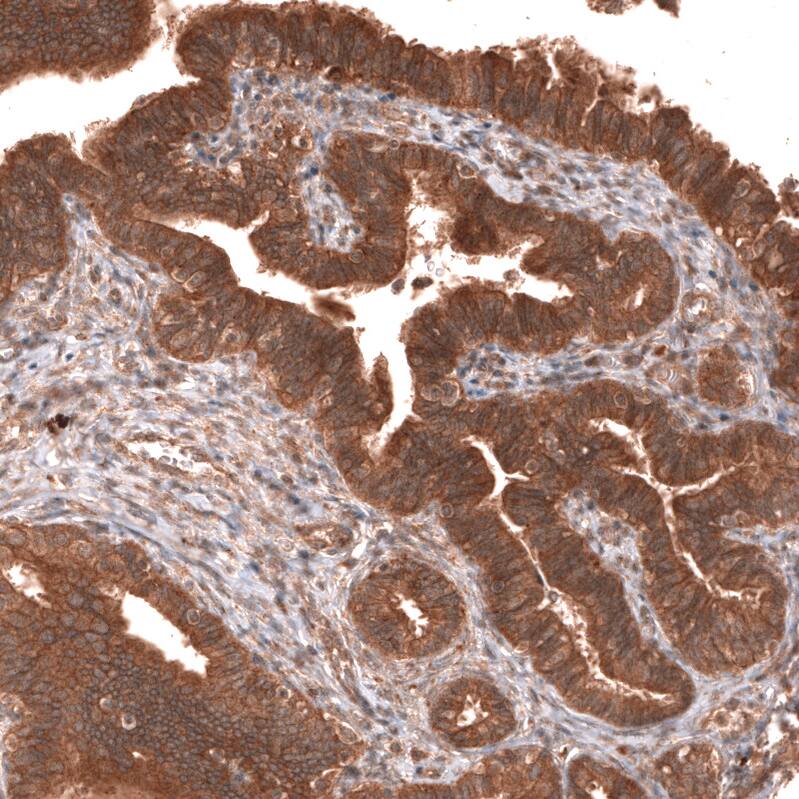

Immunohistochemistry-Paraffin: YAP1 Antibody [NBP3-43868]

Staining of human endometrium shows strong cytoplasmic positivity in glandular cells.